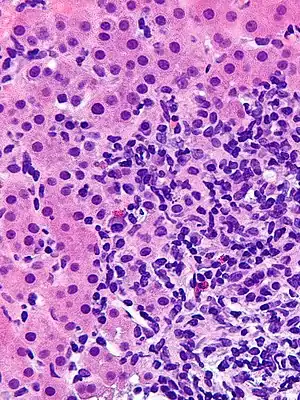

Giant cell transformation in autoimmune hepatitis